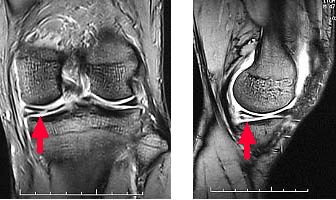

半月板損傷

前十字靭帯損傷

後十字靭帯損傷